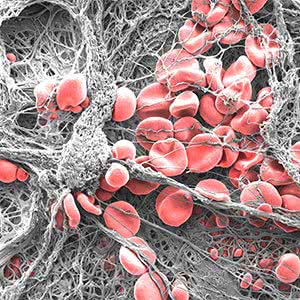

Clotted

Eli Moore

Centre for Cancer Biology